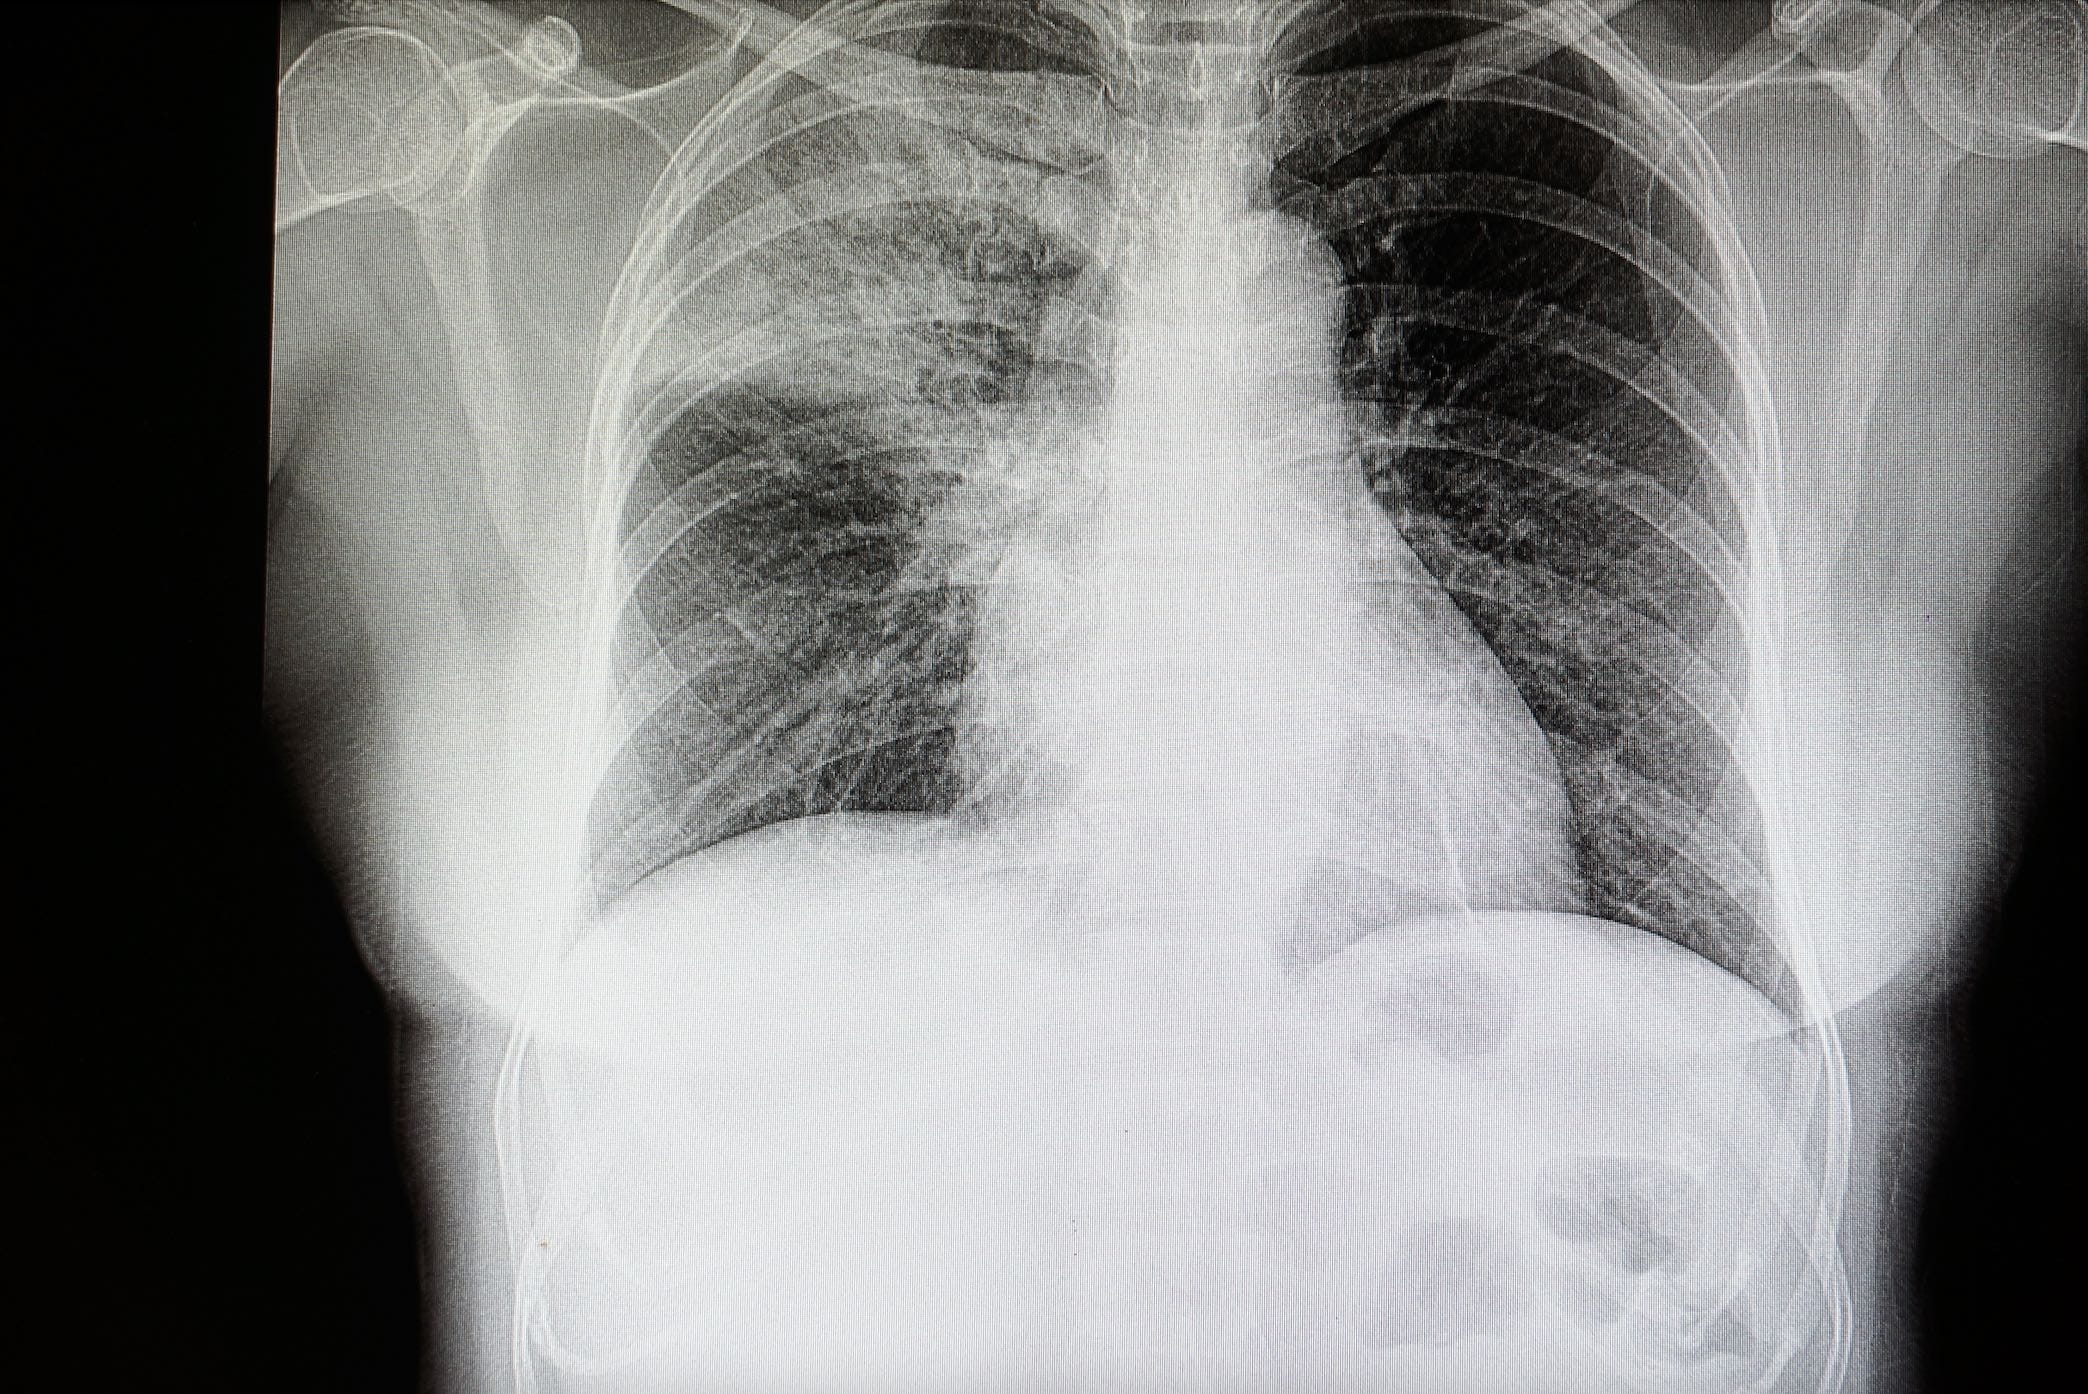

Chest x-ray Typical pneumonia —  Patchy or lobar infiltrate (opacity)

Chest X-ray Atypical pneumonia — Patchy non- lobar infiltrates

This is necessary for confirmation of diagnosis and for early detection of complications e.g. pleural effusion and empyema.

Radiological changes lag behind the clinical course so that x-ray changes may be minimal at the start of the illness. Usually, radiological changes appear 12-18 hours after the onset of illness. Conversely, consolidation may remain on the chest x-ray for several weeks after the patient is clinically cured. However, a chest x-ray should always return to normal by 6 weeks. Persistent changes on chest x-ray after this time suggest a bronchial abnormality, usually a carcinoma, with persisting secondary pneumonia.

X-ray chest may show patchy or homogenous opacity localized to the affected lobe or segment. However, the pattern of radiographic abnormalities is not specific to any particular cause of pneumonia.